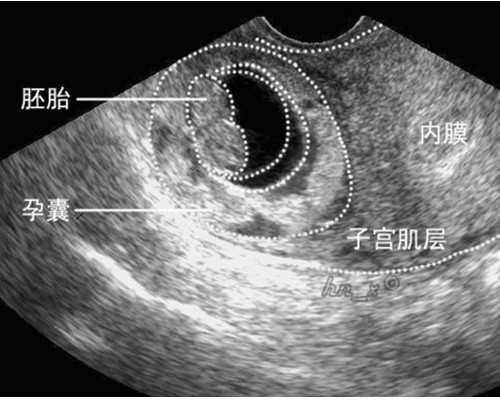

试管婴儿设备和技术水平对成功率有很大影响。在选择私立机构时,我们需要注意其拥有的设备是否先进,是否具备应用最新研究成果的能力。同时,还要了解该机构是否配备了高素质的技术人员,是否能够提供全面细致的治疗服务。